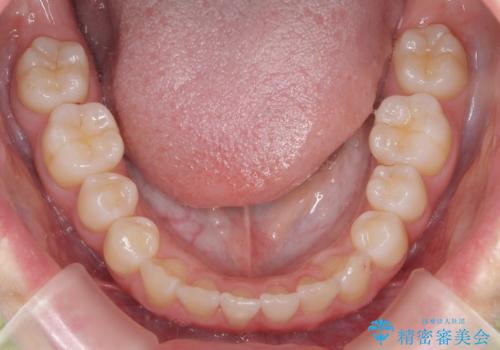

- 前歯が出ていることを主訴に来院。

歯を抜かずにマウスピース矯正をご希望でした。

歯と歯の間をわずかに削り、歯並びを少し横に拡大して並べました。

奥にすき間がなかったため後ろには下げていません。

沢山ひっこめるには4本抜歯でワイヤーの選択肢もありましたが、抜かないでできる範囲をご希望されました。

とがった形の歯列を整えるだけでもだいぶ印象は変わると思います。

今回歯列を広げた結果、上顎犬歯の歯肉は多少退縮しています。